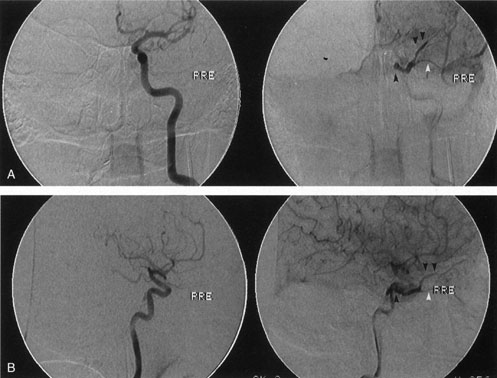

Most capillary hemangiomas can be diagnosed readily by clinical inspection. However, if delineation of the extent of deep orbital involvement is required, or the diagnosis is unclear, magnetic resonance imaging (MRI) with surface coils, gadolinium–pentetic acid enhancement, and fat suppression (to detect enhancement against the orbital fat) is indicated. The tumor is isointense to muscle and gray matter on T1- and hyperintense on T2-weighted images.22 The enhancement seen with intravenous contrast varies from moderate to intense and may be homogeneous or inhomogeneous.10 Lesions undergoing involution are less intense and more inhomogeneous. Major feeding vessels appear as black, serpiginous structures because of the “flow void” phenomenon.22 B-scan ultrasonography shows a smooth, lobular, or irregular mass with variable internal reflectivity that blends into surrounding orbital structures.23 A-scan ultrasonography shows alternating high internal reflectivity (high echo spikes) and low internal reflectivity (low echo spikes) resulting from the variable architecture and acoustic interfaces of vascular spaces, cellular areas, and septa, and moderate sound attenuation.24 High vascular flow may be demonstrated on Doppler echography. On computed tomography (CT) scan, the margins of deep infantile hemangiomas vary from moderately well defined to irregular.25 They can occur anywhere within the orbit and may be both intraconal and extraconal. There are no calcifications within these lesions. Occasionally, they indent the globe and are associated with bony orbital enlargement without erosion.10 Very rarely, angiography may be needed in the unusual situation where hazardous superselective embolization is used for life-threatening hemangiomas unresponsive to other therapies.20 These lesions frequently have multiple feeding vessels from both the internal and external carotid arteries.

Treatment is required for children with refractory amblyopia, threatened occlusion of the visual axis, compression of the optic nerve, or corneal exposure secondary to severe proptosis. Controversy exists about the most appropriate management of induced astigmatism and anisometropic refractive error, with some authors advocating early treatment to reverse severe refractive errors.10,26 Nonvisual indications for therapy include deep lesions that bleed frequently, secondary maceration and erosion of the epidermis, or severe disfigurement. Systemic indications for treatment are cardiovascular, hematologic, or obstructive complications.20 Intralesional corticosteroids have been the mainstay of initial therapy in lesions requiring treatment. Their therapeutic effectiveness results from arteriolar constriction and narrowing of precapillary sphincters.27 Combinations of short- and long-acting corticosteroids of various doses have been successful. Generally, the long-acting depot steroid is directed deep into the lesion to prevent deposits from being visible under the skin, and the more soluble short-acting corticosteroid is given subcutaneously around the periphery of the capillary hemangioma. Injections usually are given under mask inhalation; separate 1- to 3-mL syringes with 25- or 27-gauge needles are used for each substance. The following are two popular regimens: (a) 40 mg triamcinolone acetate and 6 mg betamethasone given separately into the lesion28 or (b) 40 mg methylprednisolone and 4 mg dexamethasone sodium phosphate given separately into the lesion.9 Some authors vary the dose according to the size of the capillary hemangioma.29,30 Involution of the tumor may begin several days after injection and usually is considerable within 2 to 4 weeks.26 Injections can be repeated at 6-week intervals, as needed.9,30 Intralesional corticosteroids are effective in inducing moderate to marked involution in 45% to 88% of cases,20,26,30 but recurrence and regrowth with diminution of the steroid dose is not infrequent. Potential complications of intralesional steroids include adrenal suppression, blindness secondary to retinal embolization of the corticosteroid, eyelid depigmentation, eyelid necrosis, and subcutaneous fat atrophy.31–34 Other treatment modalities include topical steroids, sub-Tenon infusion of steroids, systemic corticosteroids, laser therapy, interferon injections, selective arterial embolization, and surgery.20,35–37 Topical clobetasol propionate cream given twice daily for 2 weeks, with 1 week drug-free periods, may be an alternative mode of treatment in those patients whose parents decline intralesional steroids.37 Promising results without fibrosis or hypertrophic scarring have been reported with repeated treatments using the flashlamp pumped-pulsed dye lasers, particularly if initiated early, when lesions are relatively flat.38 Interferon alfa, which inhibits both endothelial cell and fibroblast proliferation, has been used for life-threatening hemangiomas resistant to corticosteroids.39,40 Hastings and colleagues examined 40 patients aged 2 to 36 months with life- or organ-threatening hemangiomas treated with daily subcutaneous interferon alfa-2b for 3 months, followed by taper or retreatment. An average 82% reduction in tumor volume occurred, with clinical response observed at an average of 6 weeks.40 Therapeutic arterial embolization is particularly hazardous and has yielded inconsistent results; it is therefore a last resort for life-threatening situations.20 Early surgical intervention in infants 2 to 20 months for selected hemangiomas without a significant cutaneous component has been reported with good results.25,35,41 Preoperative radiologic tests (magnetic resonance angiogram, arteriogram, or digital intravenous arteriogram) and blood typing are advisable for all patients. A true capsule is not present,35 making complete surgical excision of extensive infiltrating lesions very difficult. When surgery is performed in patients with Kasabach-Merritt syndrome (very large platelet-consuming lesions), systemic antifibrinolytic agents are needed, including aminocaproic acid or tranexamic acid. Cryotherapy, irradiation, and intralesional sclerosing agents have largely been abandoned because of inadequate effectiveness or unacceptable side effects